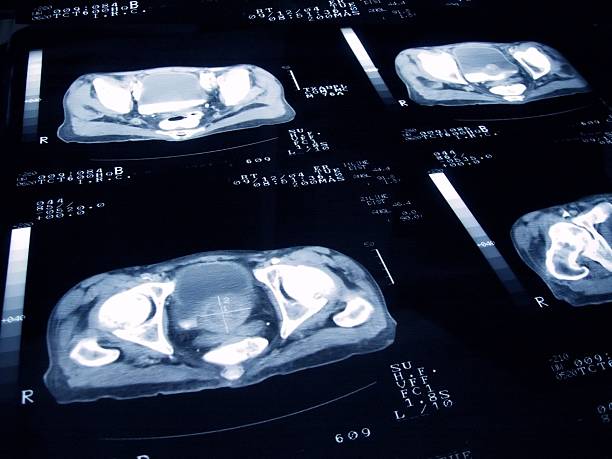

먼저 전립선염을 진단하기 위해 환자의 과거력과 증상을 검사합니다. 먼저 직장촉진, 일반소변검사, 전립선마사지 후 전립선액검사 등을 통해 원인을 찾는다. 원인이 밝혀지면 증상에 따라 약물, 식이조절, 생활습관 개선 등 손쉬운 방법으로 치료할 수 있습니다. 하지만 평소에 건강관리를 하는 것이 가장 좋으므로 담배, 술과 커피 등을 줄이며 가능한 너무 앉아 있찌만 말고 스트레칭을 하여 몸의 부담을 덜게 하는 것이 전립선을 보다 건강하게 관리할 수 있는 방법입니다.